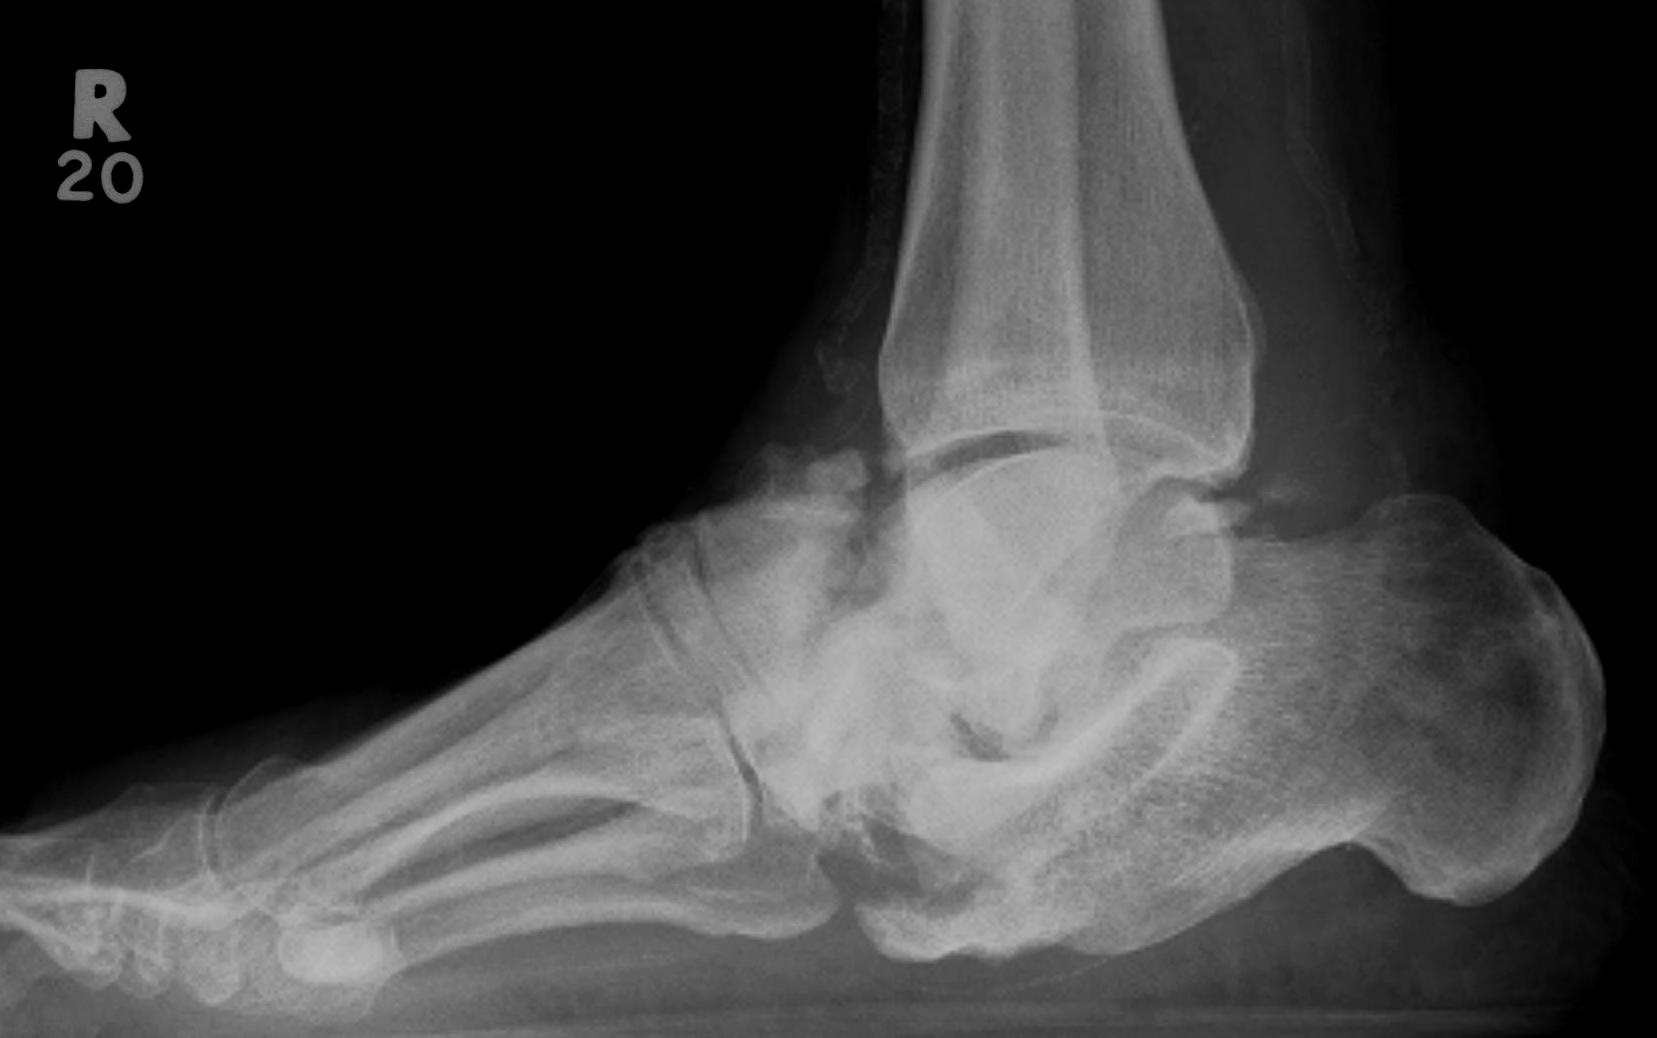

Charcot Foot & Ankle

Definition

Neuropathic Arthropathy

Progressive destructive arthropathy 2° to neurological condition

- usually minimal to no trauma

Aetiology